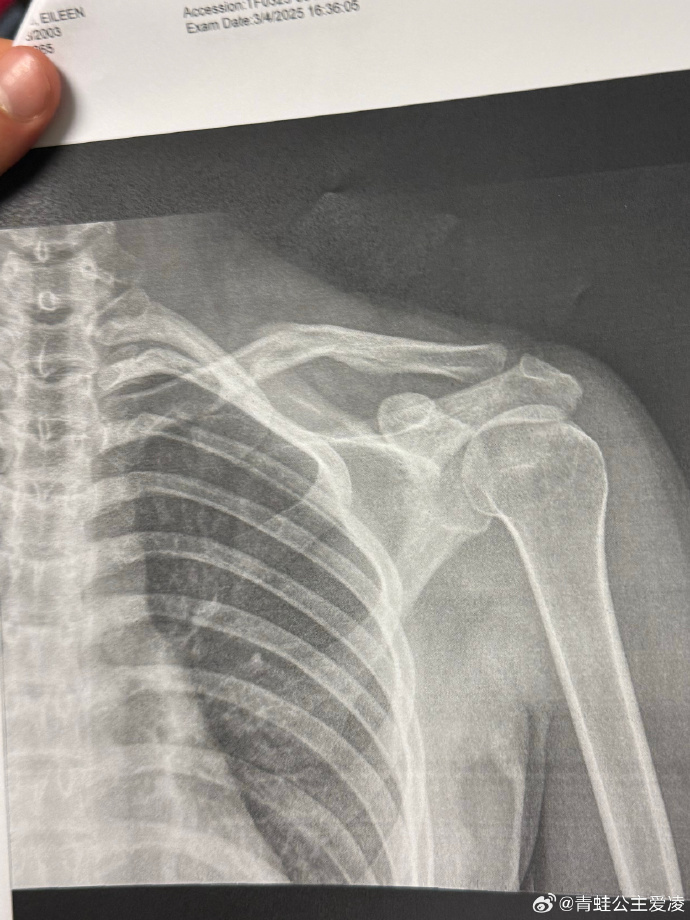

2025年3月她晒出右侧锁骨裂缝的X光片,这只是“最艰难一年”的开始。年初美国阿斯本摔伤让她休赛两月,4月才开始康复;8月新西兰训练时腰部神经损伤;11月斯图拜世界杯复出状态不佳,坡面障碍技巧赛仅列第29未晋级,世界杯排名下滑,外界质疑她的冬奥前景。